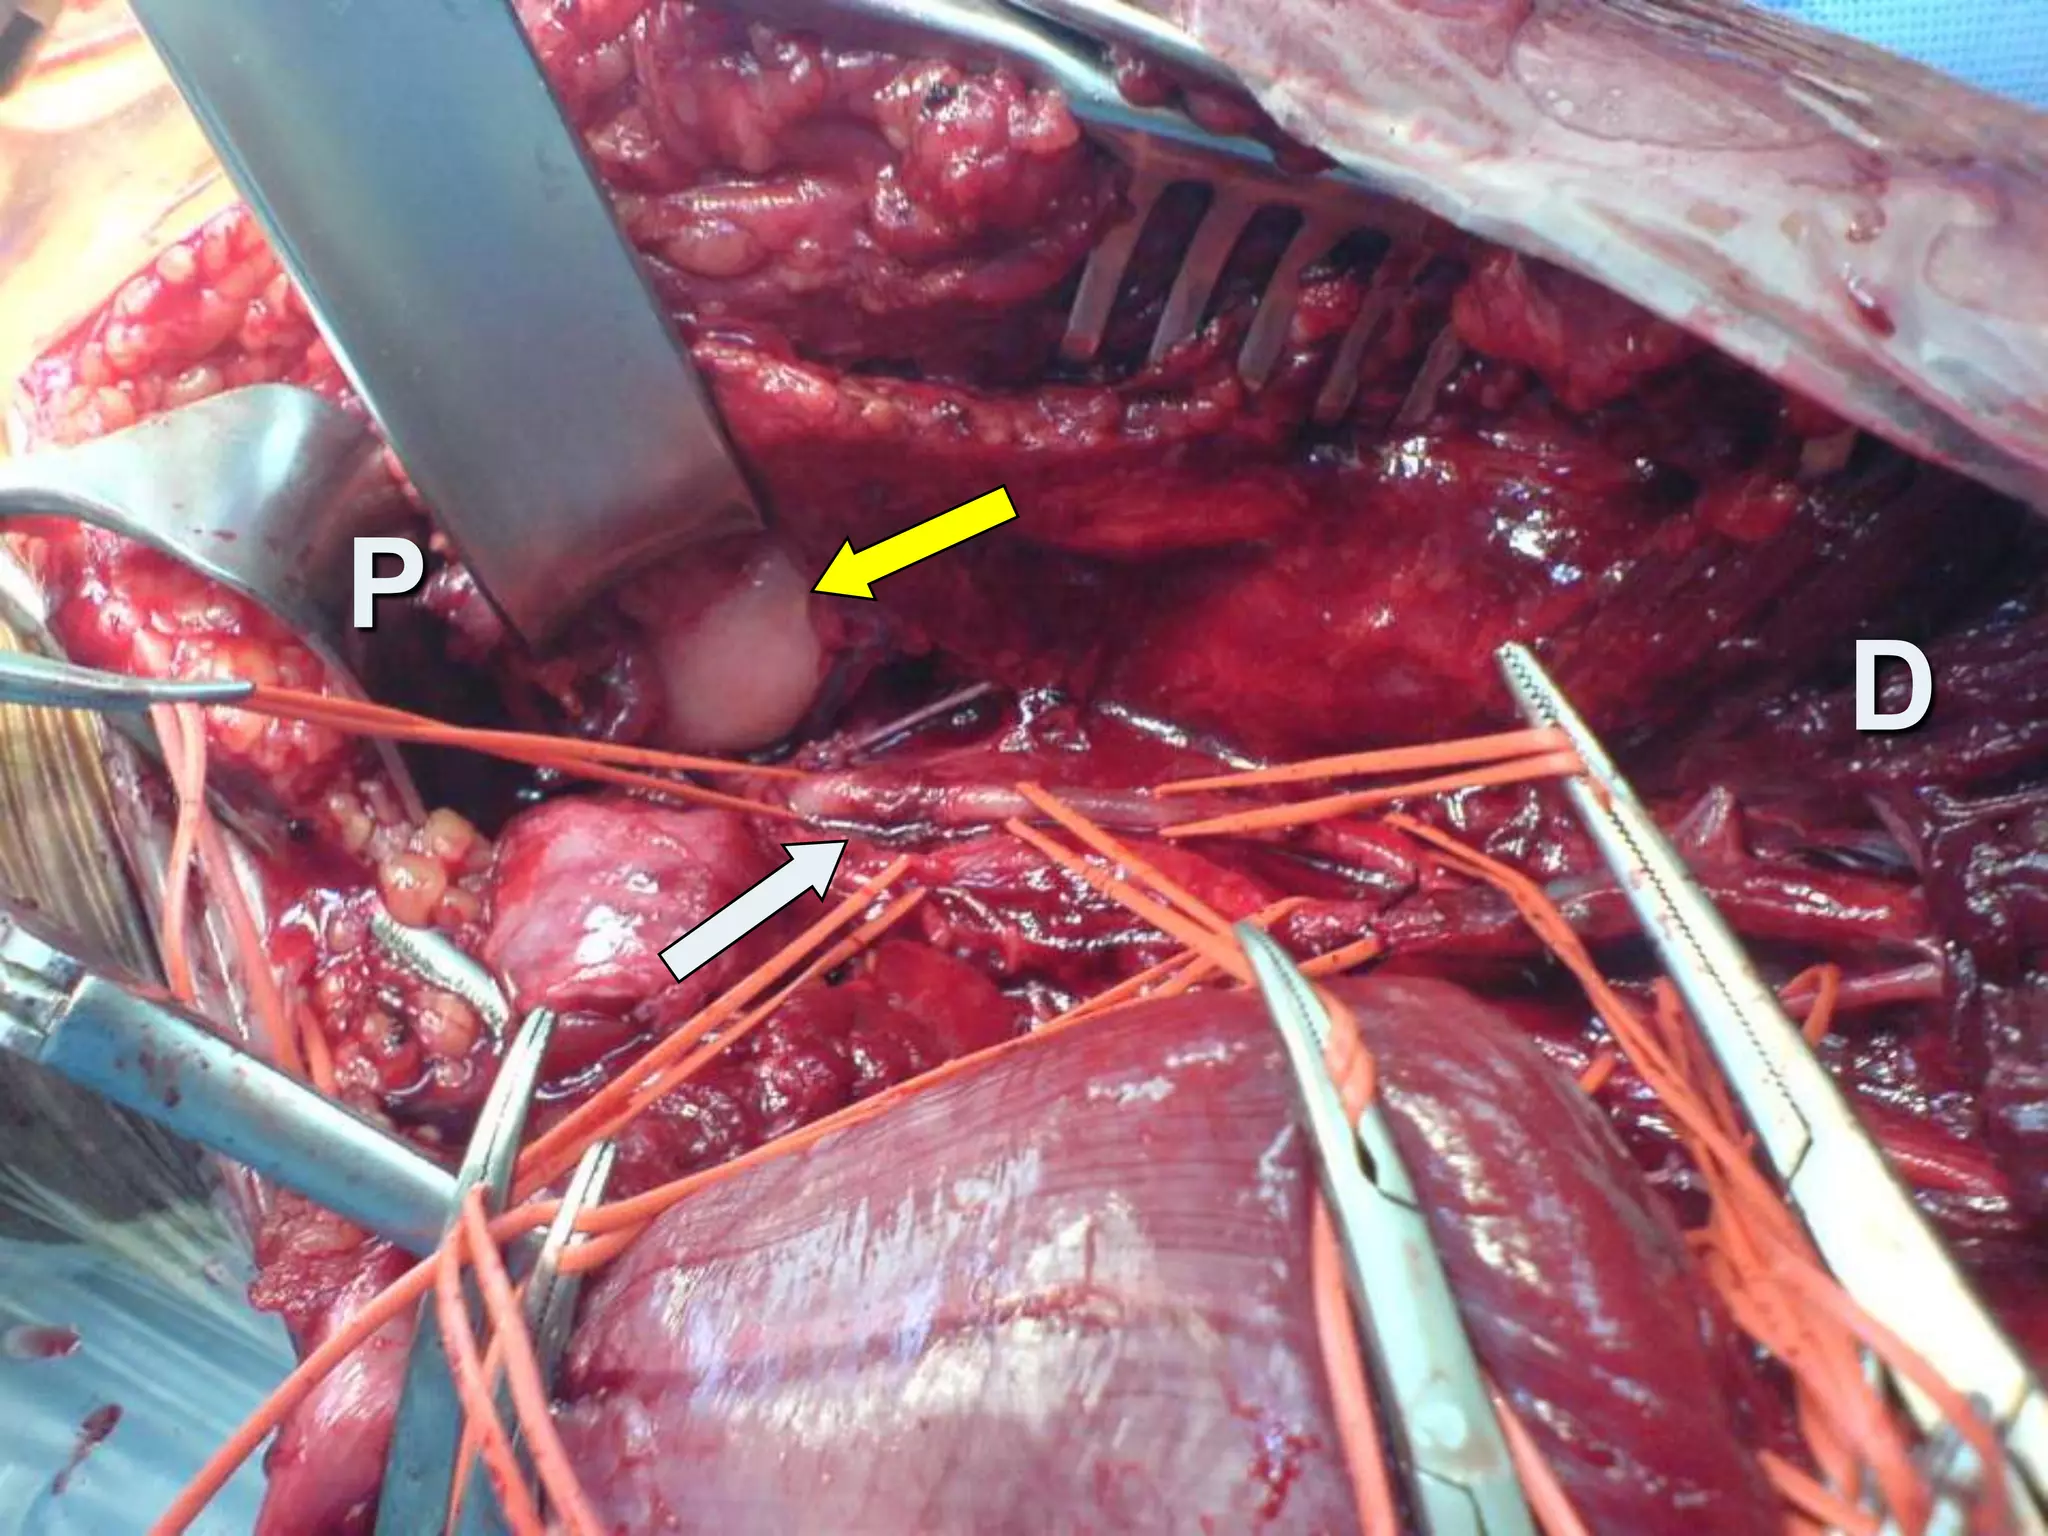

Intra-operativelyTotally transected A.Tibial atrey     (crushed distally)Contusion thrombosis T.P trunkLigation of A.Tibial artery Excision of the contused T.P trunkEmbolectomy with Fogarty cathInterposition vein grafting

Intra-operativelyTotally transected A.Tibialatrey (crushed distally)Contusion thrombosis T.P trunkLigation of A.Tibial artery Excision of the contused T.P trunkEmbolectomy with Fogarty cathInterposition vein grafting